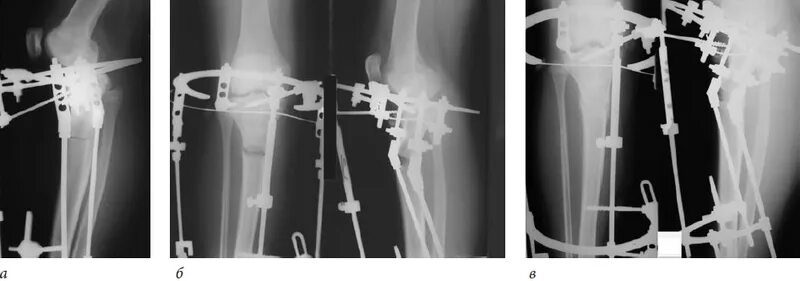

Остеосинтез мрт